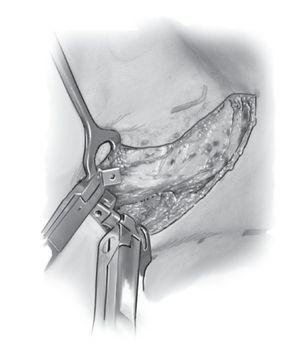

Figuras 5a y 5b. Exposición de la sinostosis costal (a) y osteotomía de la sinostosis costal con el osteótomo. El sitio de la osteotomía se distrae progresivamente con el separador laminar (b). Debe prestarse atención a desprender las adherencias costales de la pleura con un porta-algodón para que no se produzcan lesiones en la zona del pulmón.

Figura 6. El gancho costal consta de tres piezas individuales y se ensambla desde el lado proximal hacia el distal. Para acceder debajo de la costilla se usa un periostótomo para costillas.